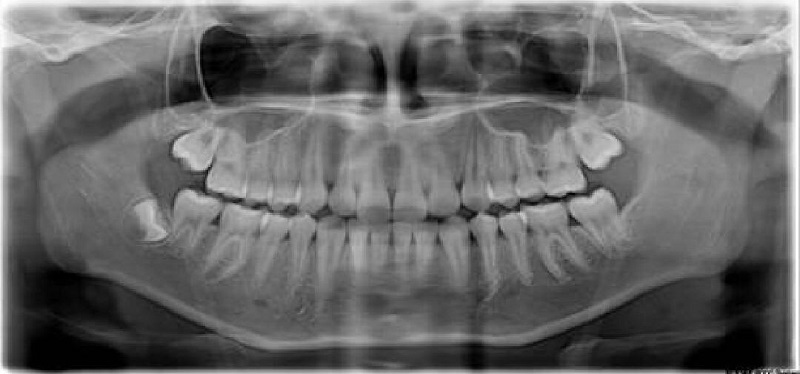

全景片(曲面断层片)

曲面断层在正畸方面应用广泛,优点是:病人从治疗开始到完成期间牙齿发育和萌出过程可以很好的评估。

病人所受到的放射剂量(包括皮肤剂量和内分泌剂量)少,对青少年特别有利,并节省时间。